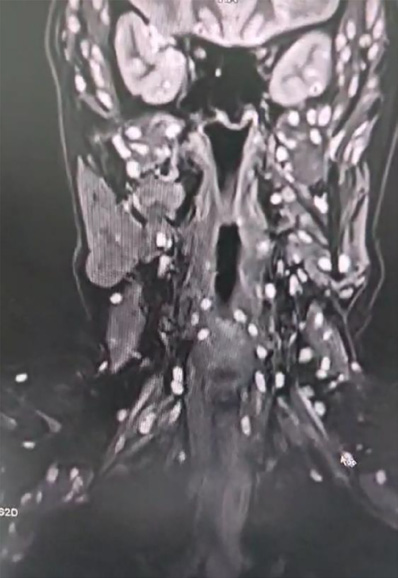

In addition, multiple cystic lesions were observed within the extraocular, facial, and tongue muscles, each containing an eccentric scolex, consistent with disseminated myocysticercosis (Figures 2 and 3). These lesions exhibited hyperintense signals on T2-weighted and hypointense signals on T1-weighted sequences, confirming their parasitic nature.

Explanation: Muscular involvement was detected through MRI, which revealed multiple cystic lesions within the extraocular, facial, and tongue muscles. The presence of an eccentric scolex inside these lesions confirmed that they were parasitic in origin, indicating disseminated myocysticercosis, which is an uncommon but clinically relevant finding.